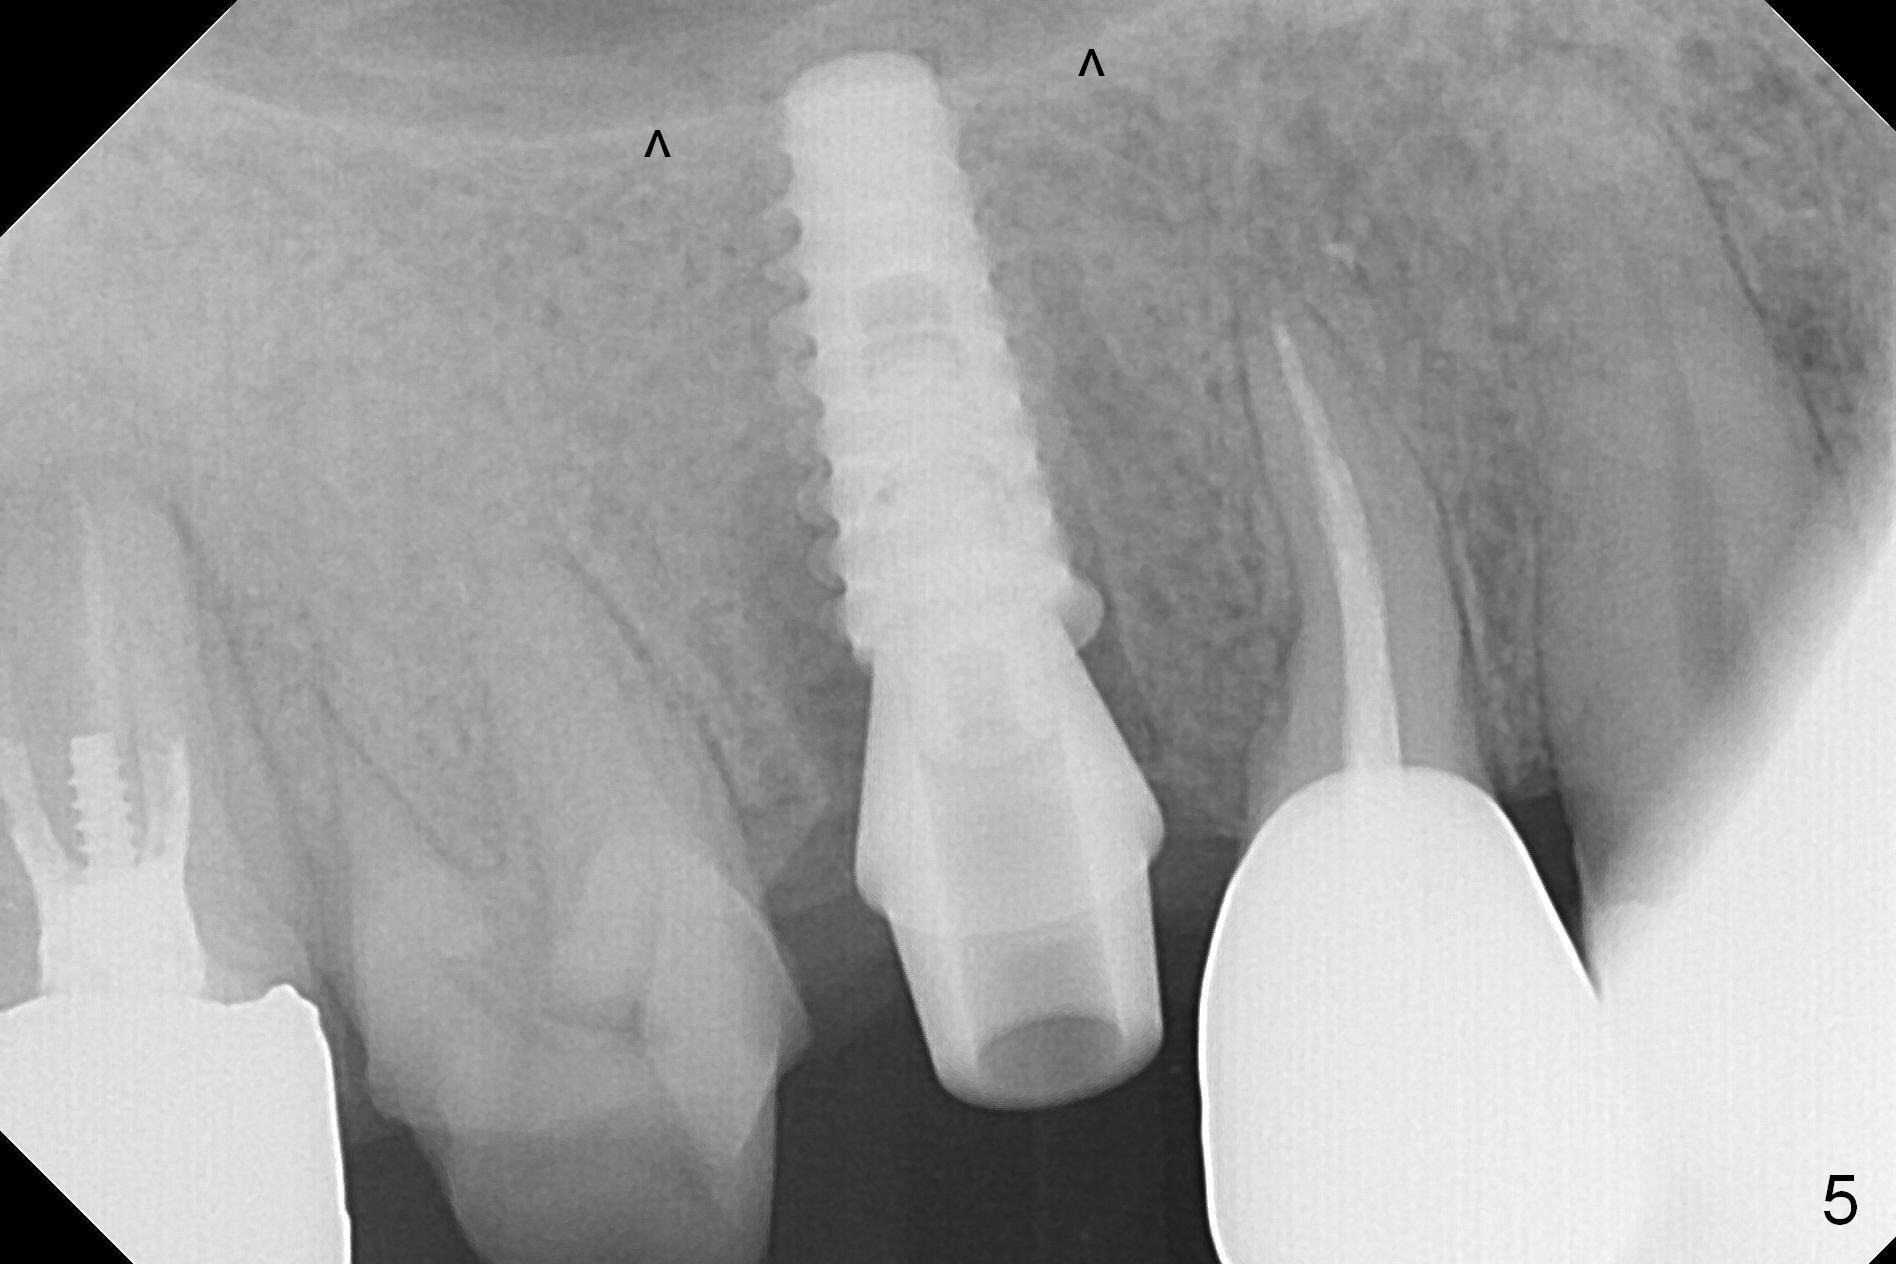

When the tooth #4 with vertical root fracture is extracted, the socket is large, approximately 6x10x10 mm (Fig.1 (mesiodistal x buccopalatal width x depth)). Osteotomy is established in the middle of the socket with 2 mm initial drill for 7 mm, 2.8 and 3.6 mm rounds drills (from DIO Sinus Master Kit) for < 7 mm, and 3.0 and 3.8 mm Magic Expanders. A 4x11 mm dummy implant is placed with insertion torque of 30 Ncm (Fig.2,3 (^: sinus floor)). There is a gap between the socket wall and the implant (*). To reduce the gap and periimplantitis, a 5x11 mm IBS implant is placed with insertion torque > 50 Ncm after further osteotomy using Magic Drills (Fig.4,5). Following placement of 5.5x4(4) mm abutment (A) and bone graft (data not shown), a splinted provisional is fabricated at #3 and 4. The provisional is stable 3 months postop (Fig.6,7). The peri-implant gaps (Fig.4,5) seem to disappear (Fig.6) with the help of bone graft. Bone graft appears to remain between the implant fins (Fig.7 arrows). Impression is taken 4.5 months postop (Fig.8,9). The abutment dislodges 4 months post cementation. After retightening, there is clearance for shim after use of 2 layers of thick articulating paper. Is the abutment screw too short? Or Titanium V is too hard for welding? The abutment/crown dislodges again 1 year 3 month post cementation; it appears that the fact that the implant is placed deep contributes to abutment screw loosening (Fig.10,11). An abutment screw will be buried inside the implant well 10 days post initial retightening.